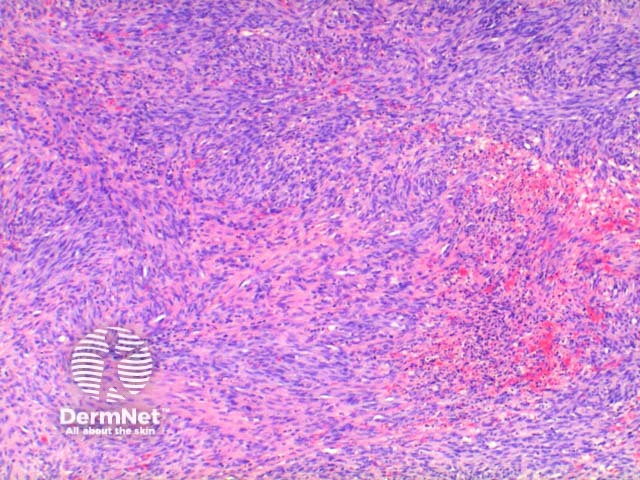

The low power view of the histology of Kaposi sarcoma is of a cellular dermal nodule (Figure 1). There may be varying degrees of overlying epidermal changes which can range from prominent hyperkeratosis and acanthosis to frank ulceration. The dermal proliferation is comprised of a spindle cell proliferation of endothelial cells forming sinuous vascular spaces. These may be sparse in patch phase lesions, progressing to fascicles of spindle cells in nodular lesions (Figures 2,3). This fascicular pattern has been likened to schools of fish. The spindle cells infiltrate through the collagen, forming slit-like spaces, especially towards the periphery of the lesions (Figure 4). Where the newly formed vessels project into an existing space the promontory sign is seen (Figure 5). This is now recognised as not being specific to this condition.

Figure 2

Figure 3